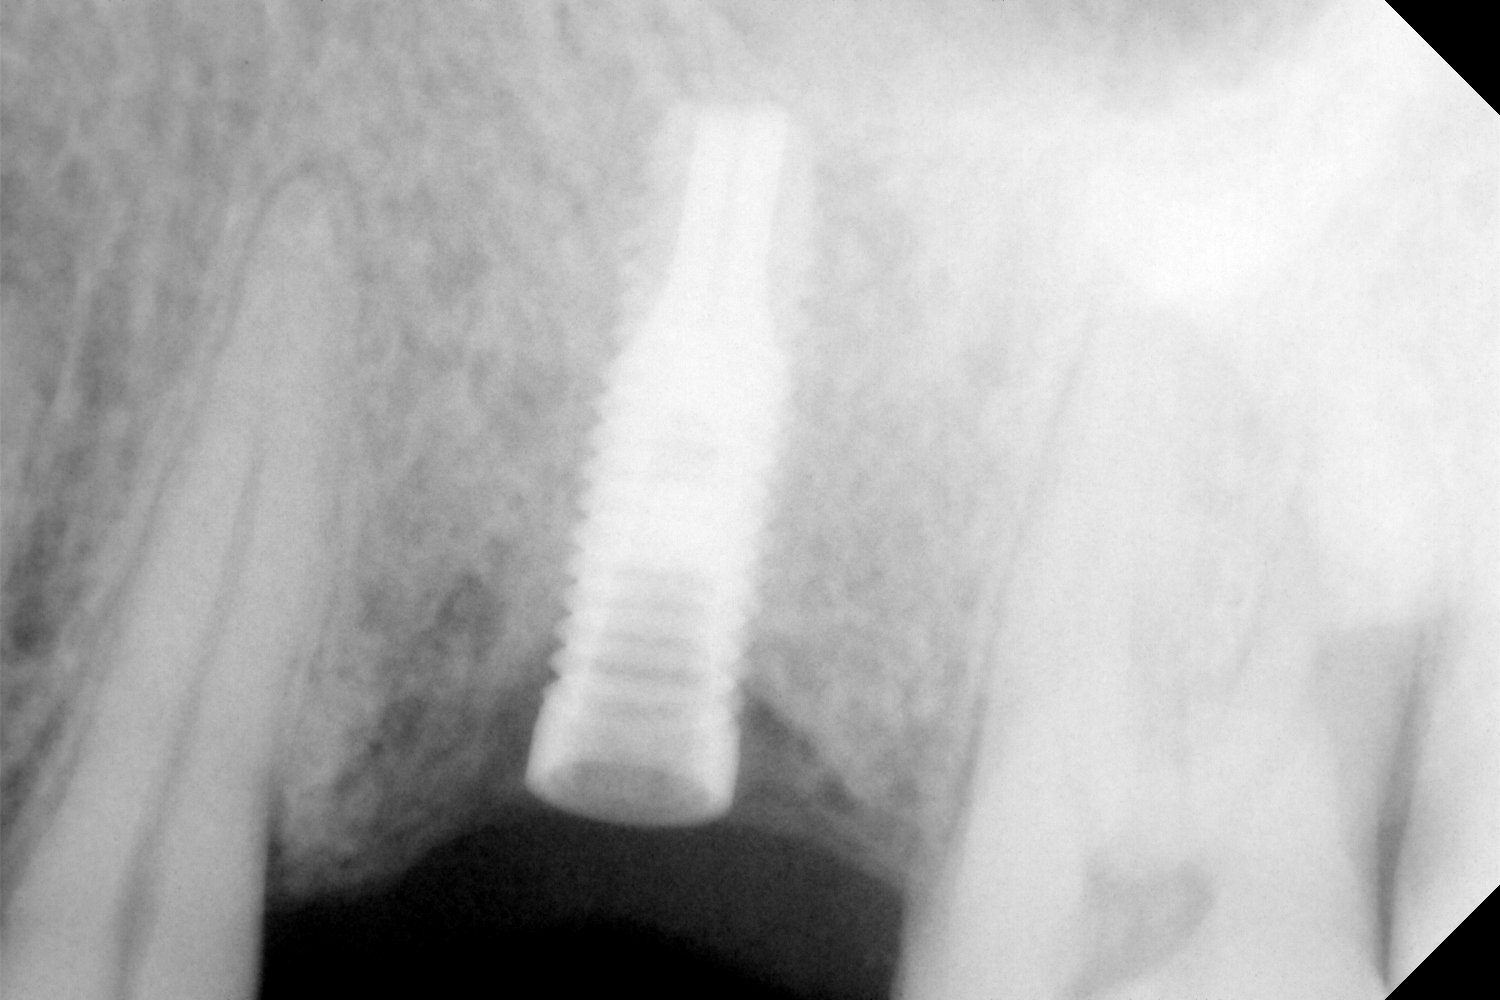

Porfavor, podrían ayudarme a identificar los tres implantes de la radiografía. ¿Que conexión tienen?. ¿Que aditamento de protesis necesitaría para poder rehabilitar los? Gracias

El implante de la izquierda no sé de que marca puede tratarse y q conexión y si es compatible con alguna otra.el 22 es un 3i conexion interna de 3.25.muchas [...]

Hola buenas tardes, necesitamos saber que implante es el de la pieza 27. Para poder colocar la corona.

Tengo que rehabilitar estos implantes. Muchas gracias de antemano